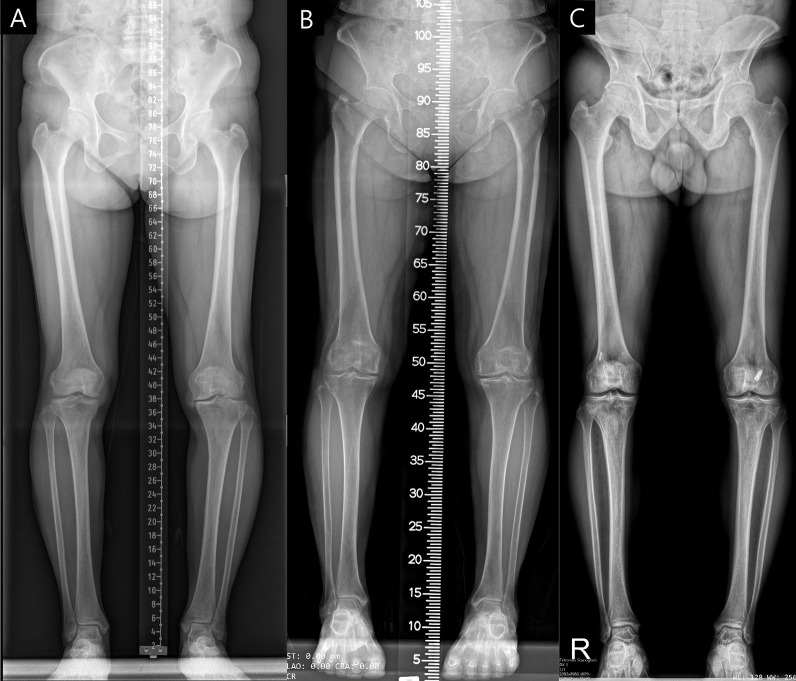

Background: Achieving consistent accuracy in radiographic measurements across different equipment and protocols is challenging. This study evaluates an advanced deep learning (DL) model, building upon a precursor, for its proficiency in generating uniform and precise alignment measurements in full-leg radiographs irrespective of institutional imaging differences.

Methods: The enhanced DL model was trained on over 10,000 radiographs. Utilizing a segmented approach, it separately identified and evaluated regions of interest (ROIs) for the hip, knee, and ankle, subsequently integrating these regions. For external validation, 300 datasets from three distinct institutes with varied imaging protocols and equipment were employed. The study measured seven radiologic parameters: hip-knee-ankle angle, lateral distal femoral angle, medial proximal tibial angle, joint line convergence angle, weight-bearing line ratio, joint line obliquity angle, and lateral distal tibial angle. Measurements by the model were compared with an orthopedic specialist's evaluations using inter-observer and intra-observer intraclass correlation coefficients (ICCs). Additionally, the absolute error percentage in alignment measurements was assessed, and the processing duration for radiograph evaluation was recorded.

Results: The DL model exhibited excellent performance, achieving an inter-observer ICC between 0.936 and 0.997, on par with an orthopedic specialist, and an intra-observer ICC of 1.000. The model's consistency was robust across different institutional imaging protocols. Its accuracy was particularly notable in measuring the hip-knee-ankle angle, with no instances of absolute error exceeding 1.5 degrees. The enhanced model significantly improved processing speed, reducing the time by 30-fold from an initial 10-11 s to 300 ms.

Conclusions: The enhanced DL model demonstrated its ability for accurate, rapid alignment measurements in full-leg radiographs, regardless of protocol variations, signifying its potential for broad clinical and research applicability.